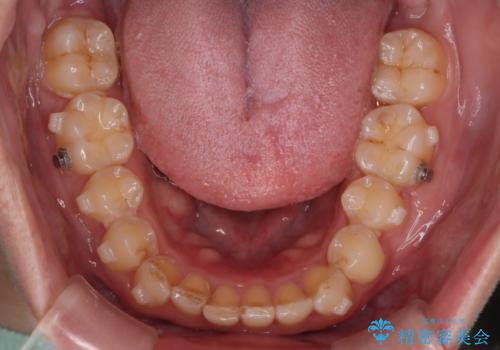

右側臼歯部の咬合改善のために、臼歯部のみ部分的なワイヤー矯正を行い、咬合改善がみられてからインビザラインにて全体的な矯正を行なっていく治療計画を立てました。

噛み合わせをよくするために、ワイヤー矯正とインビザライン矯正のどちらの期間も必要な箇所にゴム掛けを行いながら治療を行いました。